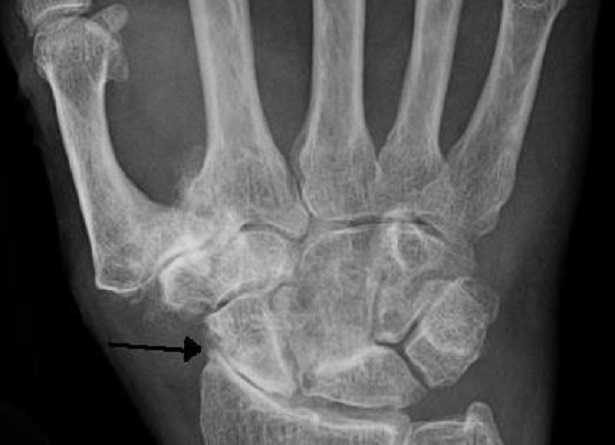

Con questo termine si indica un processo di modesta riduzione della massa ossea che porta ad una più alta probabilità di fratture visto che le ossa si rivelano man mano più sottili e deboli. Da un certo punto di vista è comprensibile che con l’avanzare degli anni questo accada a tutti, chi più chi meno, inevitabilmente, ma ad alcune persone avviene in maniera veloce, troppo veloce, tanto da poter anche arrivare a creare dei problemi.

Non ci sono in verità degli specifici ed evidenti sintomi per l’osteopenia, non da dei segni particolari, ci rende semplicemente soggetti con più probabilità alle fratture ossee. Quando un osso si rompe a causa dell’osteopenia o dell’osteoporosi, fa particolarmente male e può anche guarire con più difficoltà rispetto ad una frattura da trauma.

L’osteopenia da invecchiamento può essere naturale e sopportabile, quello che in ogni corpo accade è che la massa ossea rimane stabile ai valori massimi tra il 3° e il 4° decennio di vita, poi man mano cala perché l’attività delle cellule responsabili della formazione di nuovo tessuto osseo si riduce mentre quella delle cellule deputate all’osteolisi resta uguale. Le zone che di solito subiscono una perdita di massa ossea più pronunciata sono le epifisi, le vertebre, le ossa mascellari e la mandibola, questo processo rende più fragili gli arti e può anche far perdere i denti.

Ci sono casi di osteopenia che emergono anche nel contesto dell’osteite fibrosa cistica, condizione causata da iperparatiroidismo e caratterizzata da fibrosi midollare. In caso di frattura e di conseguente immobilizzazione prolungata di un arto o di un osso in generale, può sì comparire l’osteopenia ma spesso è momentanea.